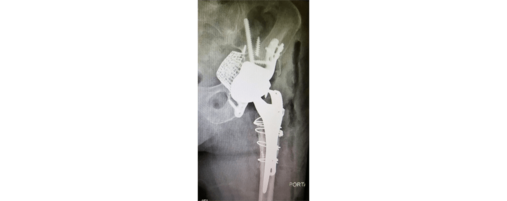

With more than 35,000 individual solutions during the last 50 years. We helped many patients regain their quality of life.